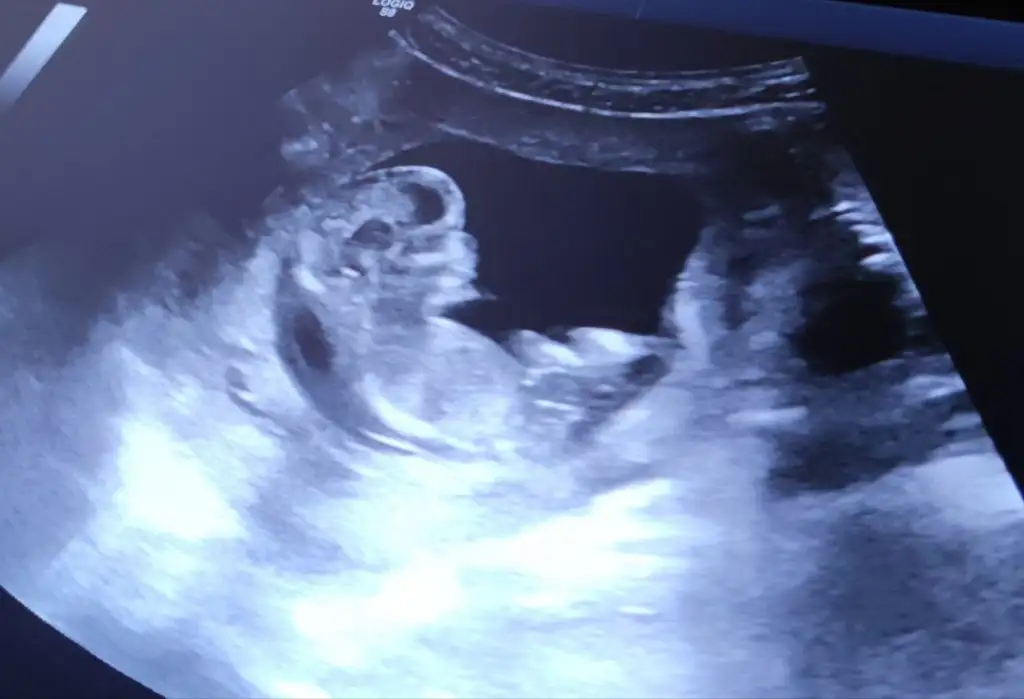

Çoook uzun bir süre araştırma okuma yaptıktan sonra sizlere bu başlığı açtım çevremde tüm gebelere de denedim. Bunun sırrını çözen İnstagramda (isim vermeyim) işi ticarete dökmüş bile.Nub, Ramzi,Çin Rus Japon Takvimleri, Yüzük Yöntemi bir çok şey size sayabilirim.

5 ve 14. haftaya kadar olan ultrason fotolarınızı paylaşın. Vajinadan mı yoksa karından mı çekildiğini ve kaç haftalık olduğunu da mutlaka belirtin.

Not: Tahmin yaptığım anneler cinsiyet öğrendikten sonra lütfen bana geri dönüş yapın![]()

Benim kızmış canımkuzucum erkek bebiş gibi görünüyor hakkında hayırlısı :) geri dönüş yapmayı unutma![]()